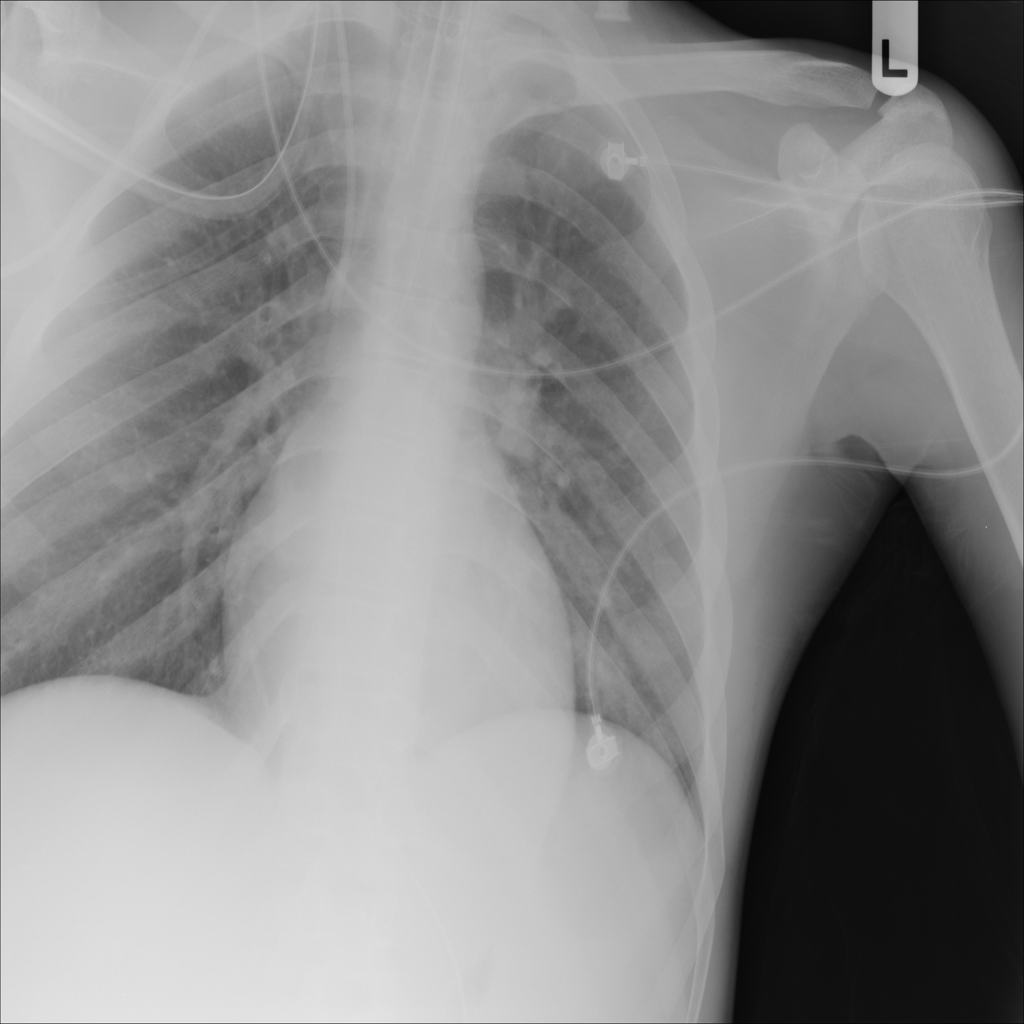

PAT-A1E2 · IMG-001Pneumonia

PAT-A1E2 · IMG-001

AP